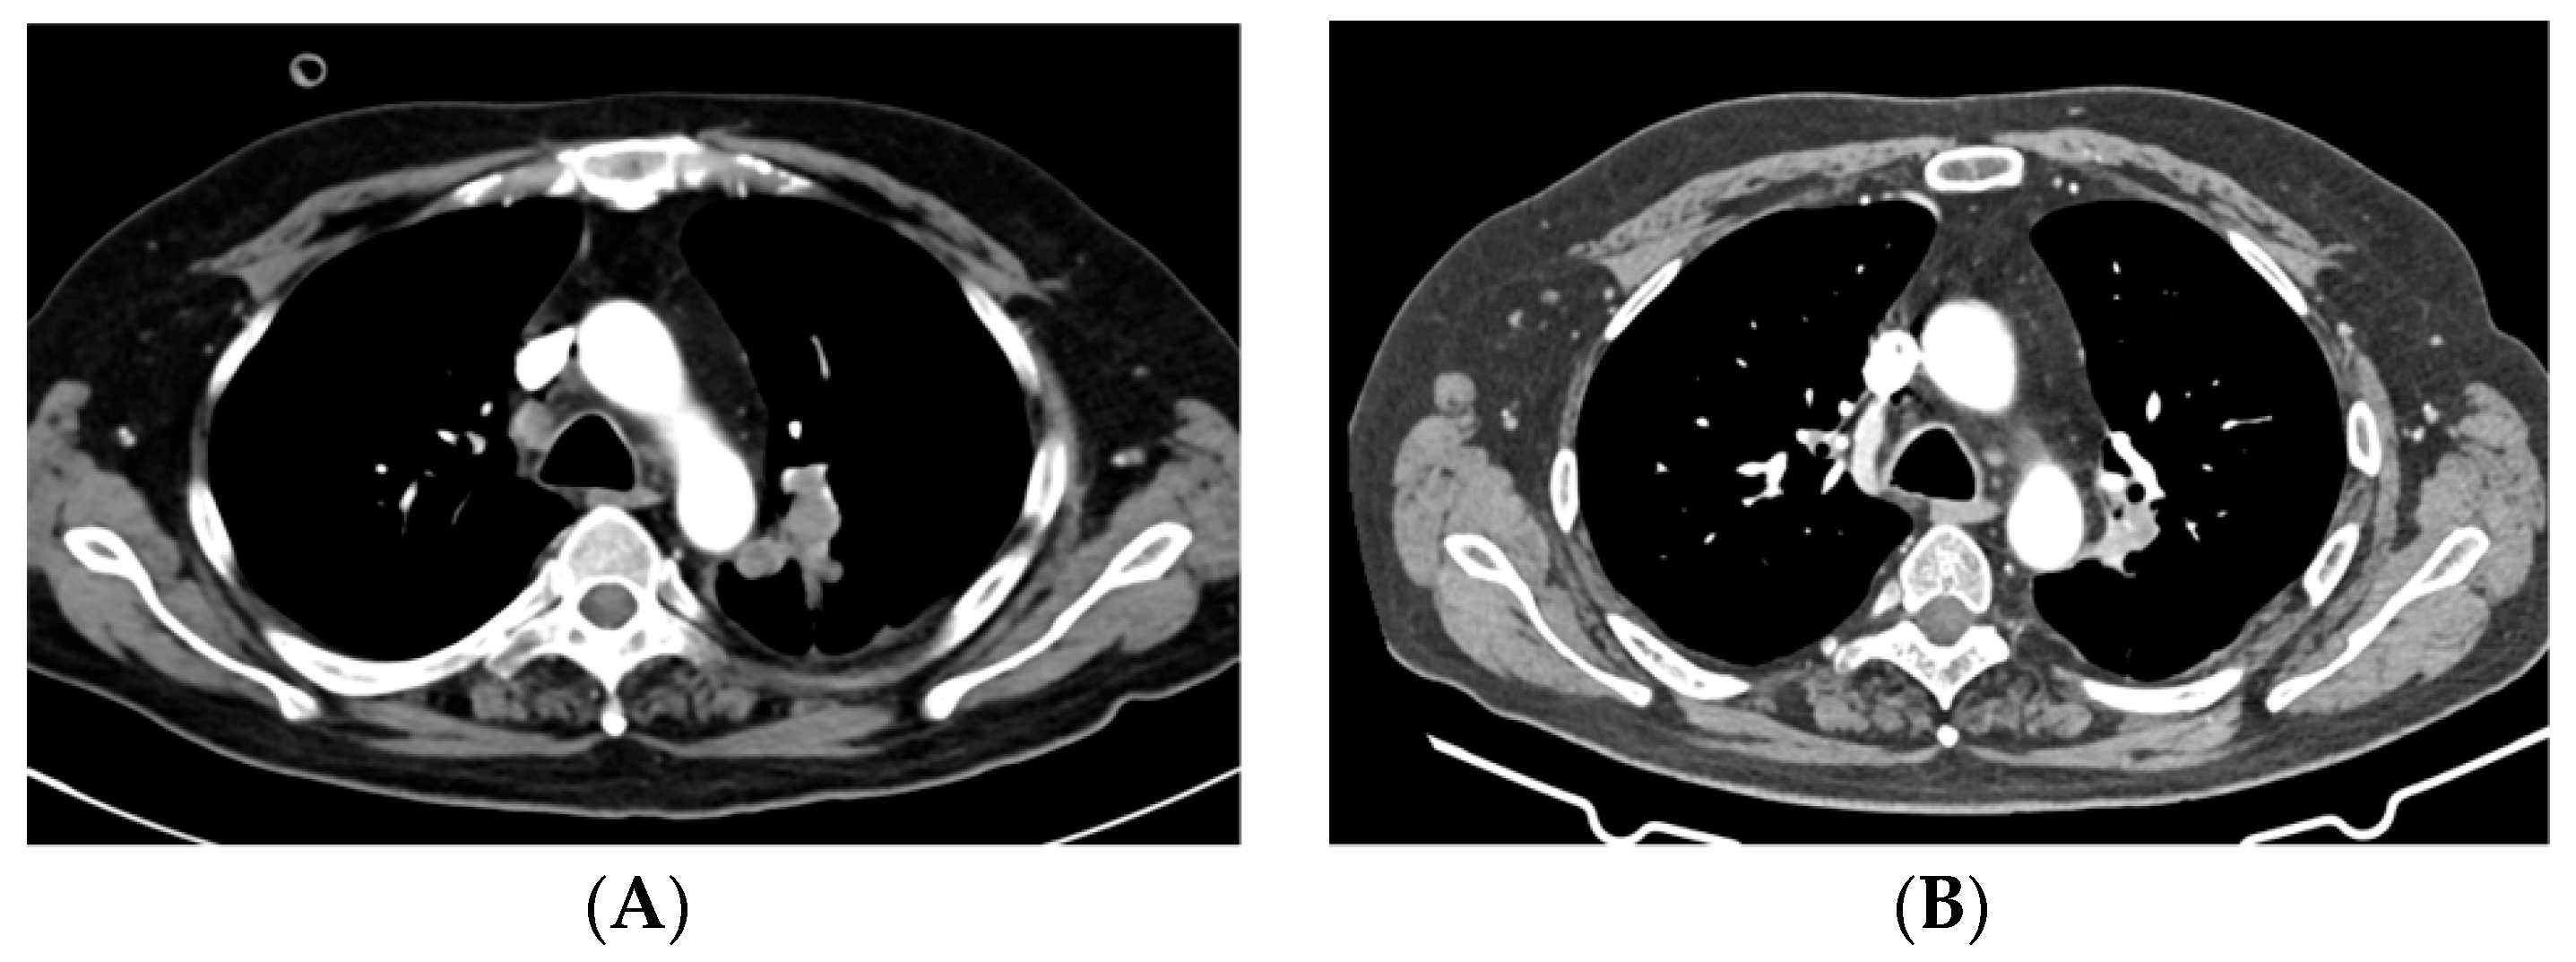

2.1. Case 1

2.2. Case 2

2.3. Case 3